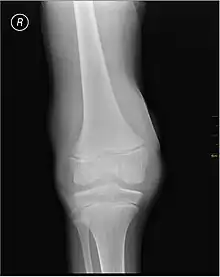

- X-ray of Hemarthrosis